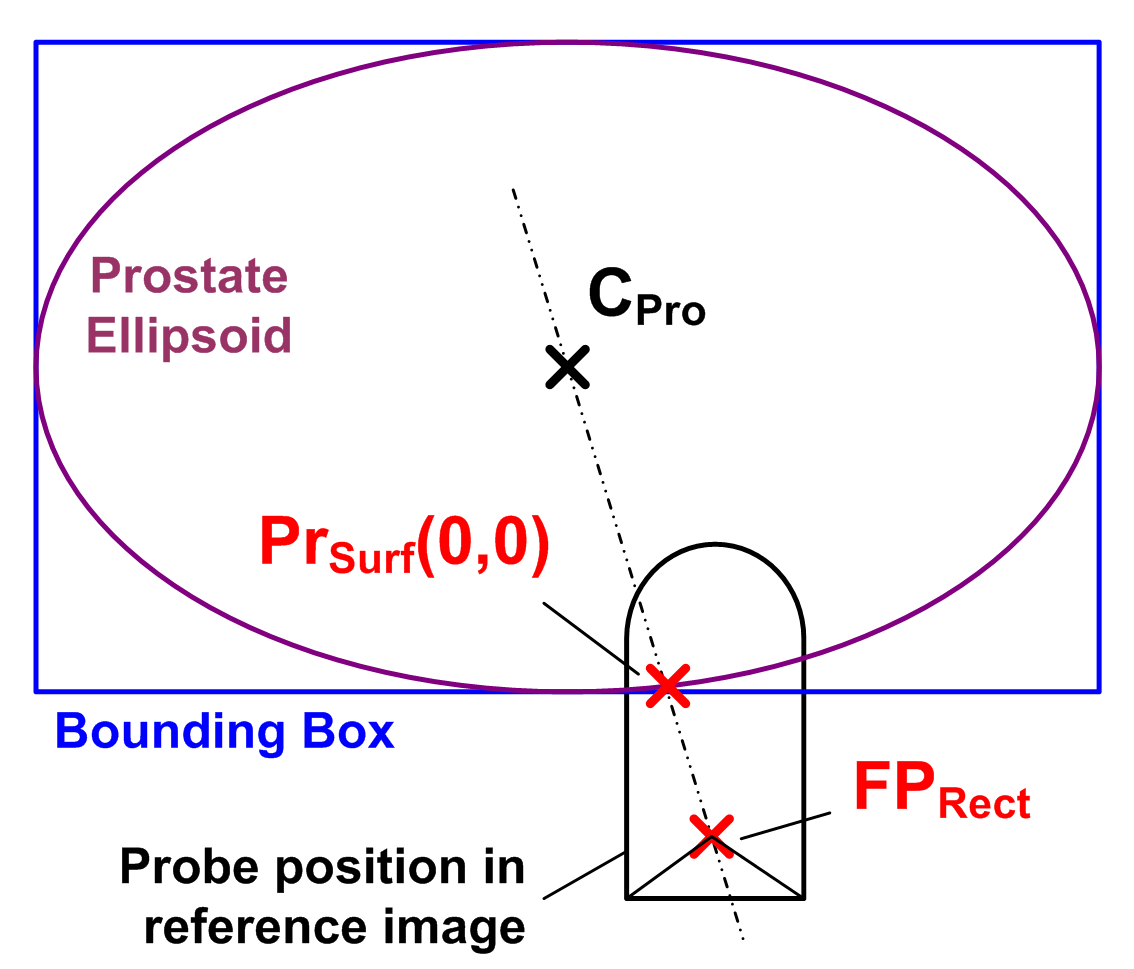

With these assumptions it is possible to define a probe movement model based on a prostate surface approximation, the probe position in the US image (which is known) and a rotational fixed point in the rectum. As shown in Fig. 1, the prostate surface is approximated by a bounding-box aligned ellipsoid. The ellipsoid is modeled using a 2D polar parameterization . The origin of the parameterization corresponds to the intersection of the line from the prostate center to . As illustrated in Fig. 1, implements assumption 1) by determining plausible US transducer positions on the prostate surface. Assumption 3) is satisfied by requiring that the principal probe axis must always pass through . Finally, a rotation about the principal probe axis implements assumption 2) and thus adds a third DOF (See Fig. 1).